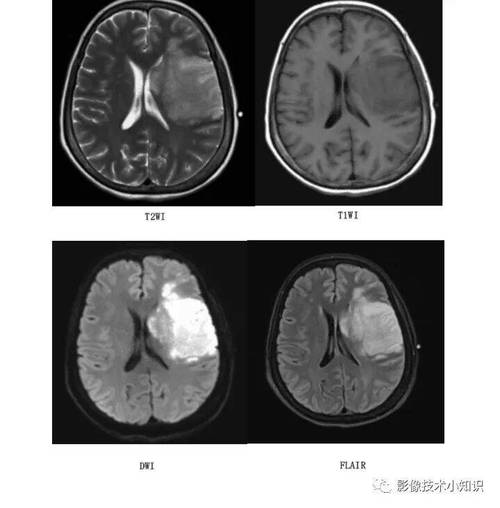

- 在脑梗中的应用:MRI能非常敏感地早期发现脑组织缺血、坏死的迹象,尤其是DWI序列(弥散加权成像),能在脑梗发生后的数分钟甚至更短时间内就显示出异常信号,是诊断急性脑梗的“金标准”之一,它能告诉我们“脑组织有没有梗塞”以及“梗塞的范围有多大”。

“小血管病变”是“元凶”——最常见的原因

- 解释:MRA虽然能清晰显示颅内主要的大血管(如颈内动脉、大脑中动脉、大脑前动脉、大脑后动脉及其主要分支),但对于更细小的穿通动脉(直径约0.2-1mm)的显示能力有限,这些穿通动脉深穿脑组织,主要负责供应基底节、丘脑、脑干等关键区域的血液。

- 关联:高血压、糖尿病、高脂血症等危险因素长期损害这些小血管,导致其玻璃样变性、纤维素样坏死或管腔闭塞,从而引起其供血区域的 small deep infarct(小深部梗塞),也就是我们常说的“腔隙性脑梗塞”,MRA大血管可能完全正常,但MRI却能清晰显示这些微小的梗塞灶。